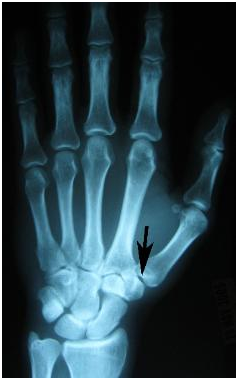

Osteoarthritis or degenerative arthritis, is a degenerative arthropathy. It involves degradation and destruction of the joint cartilage and bone. Symptoms include joint pain, stiffness, locking and sometimes, swelling as a result of a joint effusion. Any joint may develop arthritis. Arthritis of the thumb joint, is most common in the hand, in particular affecting the first carpometacarpal joint, ie base of thumb (Picture). This is a frequent site due to the high utilisation and it is relatively unstable. This occurs when the joint is damaged due to the cushioning cartilage of the joint surfaces wearing away. Pain at the base of the thumb occurs when moving the thumb and sometimes persists even at rest.

Diagnosis is based a combination of clinical findings as well as radiologic imaging (fig 1).